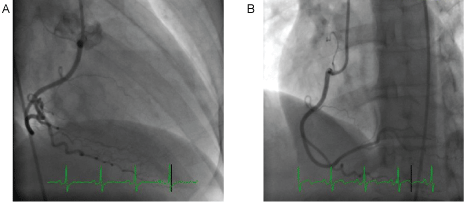

A 48-year-old woman with history of ADHD was awakened by new onset, severe chest pain which prompted her to come to the emergency department (ED). The initial heart rate was 88 and blood pressure was 147/53. There was intermittent ventricular bigeminy. Troponin I was initially undetectable and then elevated to 1.7 ng/mL six hours later, followed by a gradual decline. The initial electrocardiogram, obtained during chest pain, demonstrated normal sinus rhythm with subtle, less than 1 mm ST elevation in the inferior leads. Subsequent ECGs, obtained after chest pain ceased, showed resolution of ST segment elevation, followed by T wave inversion in the same leads”. These tracings have been added as Figure 1. Her initial echocardiogram demonstrated normal global left ventricular wall motion and normal ejection fraction. She was taken for cardiac catheterization for evaluation of NSTEMI. Cardiac catheterization revealed angiographically normal vessels (Figure 2) and mid inferior wall hypokinesis on left ventriculography (Figure 3). A spasm provocation test was not performed due to concerns about risk from induced spasm.

Figure 2: Coronary angiography of A) PDA; B) RCA showing non-obstructive coronary arteries. View Figure 2